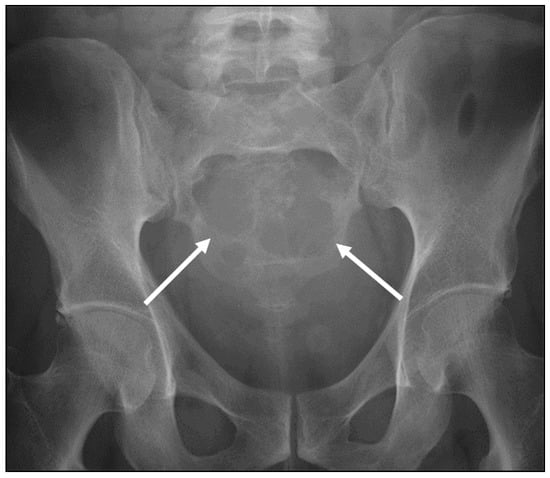

| Ewing sarcoma | Lytic lesion. Vertebral collapse. | Low to intermediate signal T1 and intermediate to high signal T2 lesion. Enhancing extra-osseous soft tissue component. |